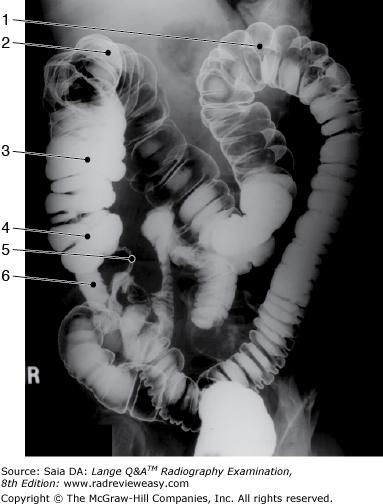

Which of the following is represented by the number 3 in the figure below?

Aorta

The structure indicated by the number 5 in Figure 6–11 is the

ileum.

The structure indicated as number 4 in Figure 2–9 is the

cecum

The structure indicated by the number 2 in Figure 6–11 is the

descending colon.